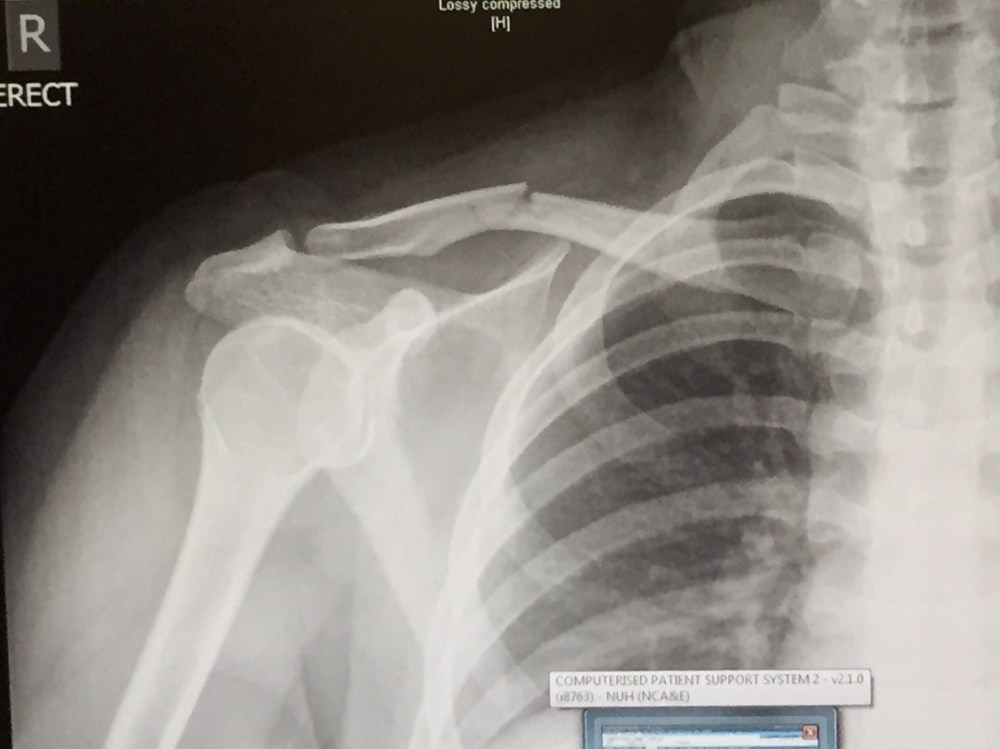

Clar Goes Out And Does Stuff, Life, University safety first Posted by Clarissa on January 24, 2015 kids, always remember to practice safe scooting habits and do not scoot down a steep hill WITHOUT BRAKING. that is all. others must know about this? well then: Share on X (Opens in new window) X Share on Facebook (Opens in new window) Facebook Share on Tumblr (Opens in new window) Tumblr Share on Pinterest (Opens in new window) Pinterest Like Loading... Related Published by Clarissa View all posts by Clarissa